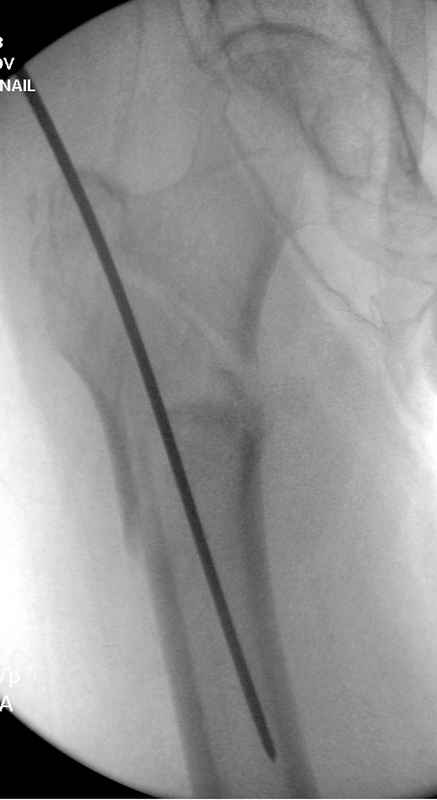

Здесь 83 года, травма в результате падения

судя по картинкам с ЭОПа явно использовались приемы непрямой репозиции под его контролем, а так же интраоперационный ЭОП-контроль положения винтов, без такого контроля операция может ухудшить ситуацию (опять же учтите сроки) т.к. результат буде зависеть в большей степени от искусства хирурга, а не от технологии